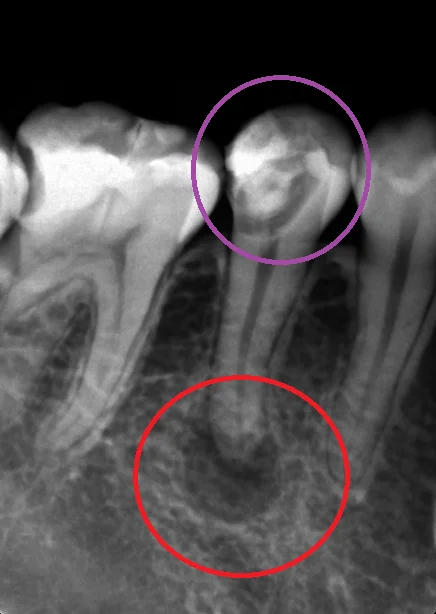

ちなみに、こちらが術前のレントゲンです。

保険内の白い詰め物のコンポジットレジンを行っているようですが、全く合っておらず、中で虫歯が大きくなっています。(紫の〇の所)

そしてそれが神経に達して、根の先に膿が溜まっています。(赤の丸の所)